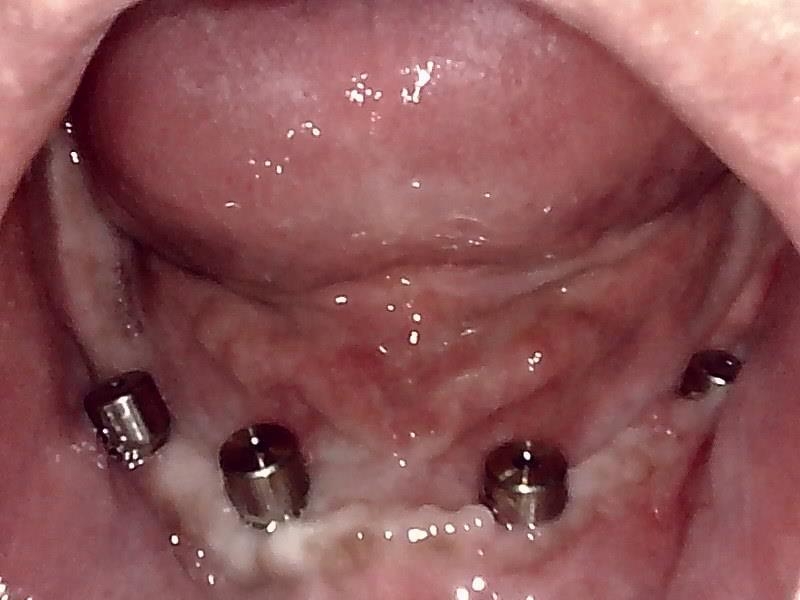

ヒーリングアバットメント装着して歯肉を縫合した状態です。

抜糸後の状態です。